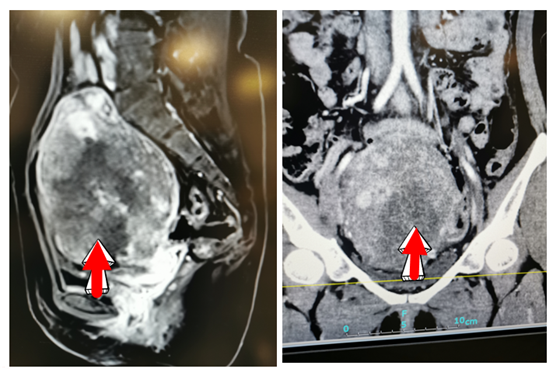

患者病灶影像图(上皮样滋养细胞肿瘤)

为此,梁丽凌教授和病理科主任彭劲武教授组织两个科室再次讨论,进一步完善免疫组化,拨开疑云,诊断终于明朗。陈女士罹患的正是极为罕见的“上皮样滋养细胞肿瘤”,由于显微镜下形态学与鳞癌高度相似,二者极易混淆。